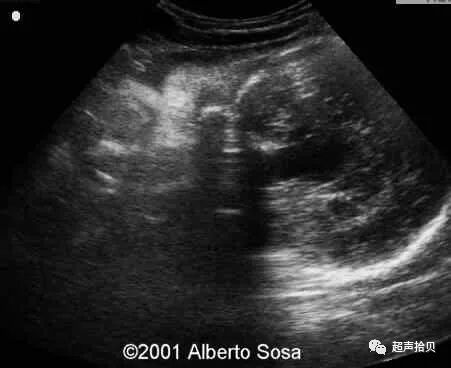

图1:横向声像图显示位于中线蛛网膜囊肿(C), 彩色多普勒没有血流显示;

图2:冠状超声图显示位于后颅窝蛛网膜囊肿